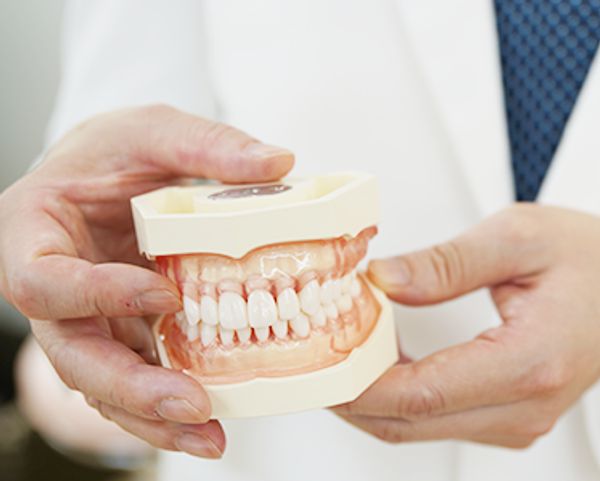

患者さまにわかりやすい

説明をしています

初回のご相談時間をたっぷり60分取っています。入れ歯治療といっても、患者さま一人一人のお口の状態は異なっています。歯並びやかみ合わせの状態によって、入れ歯の種類や治療の方法が変わってきます。これらの方法について、画像や写真を使って、各診療台に設置したモニターで説明し、納得していただいた上で治療を行っています。